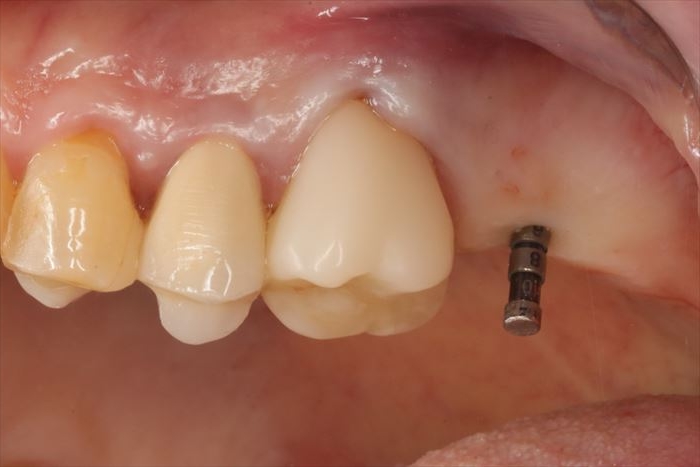

局所麻酔後、サージカルステント(ドリルガイド)の適合を確認します。

_

φ2.2㎜のパイロットドリルでドリリングを行い、深度ゲージを挿入して

デンタルレントゲン写真を撮影して確認します。